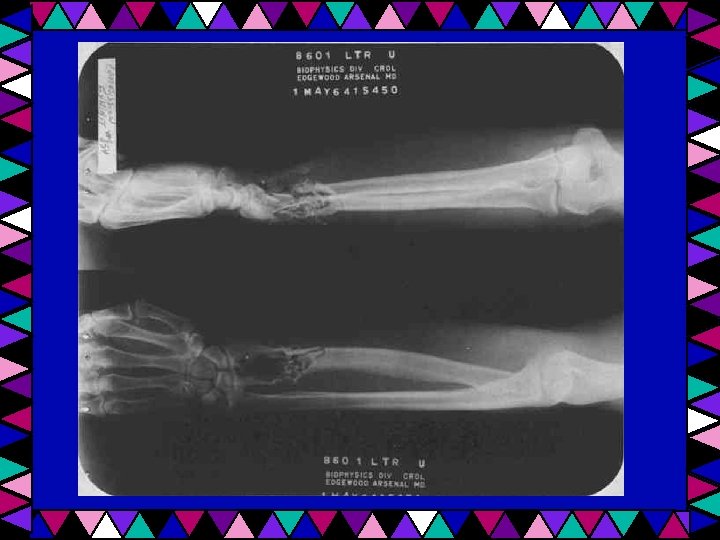

Homeostatic Imbalance Fracture – a break in the bone Open fracture – bone penetrates through the skin Closed fracture – bone does not penetrate skin

Fracture treatment • Closed reduction – When a physician pulls on bone to realign bone ends • Open reduction – When a physician surgically inserts pins or wires to realign bones

Open Reduction - Mandible